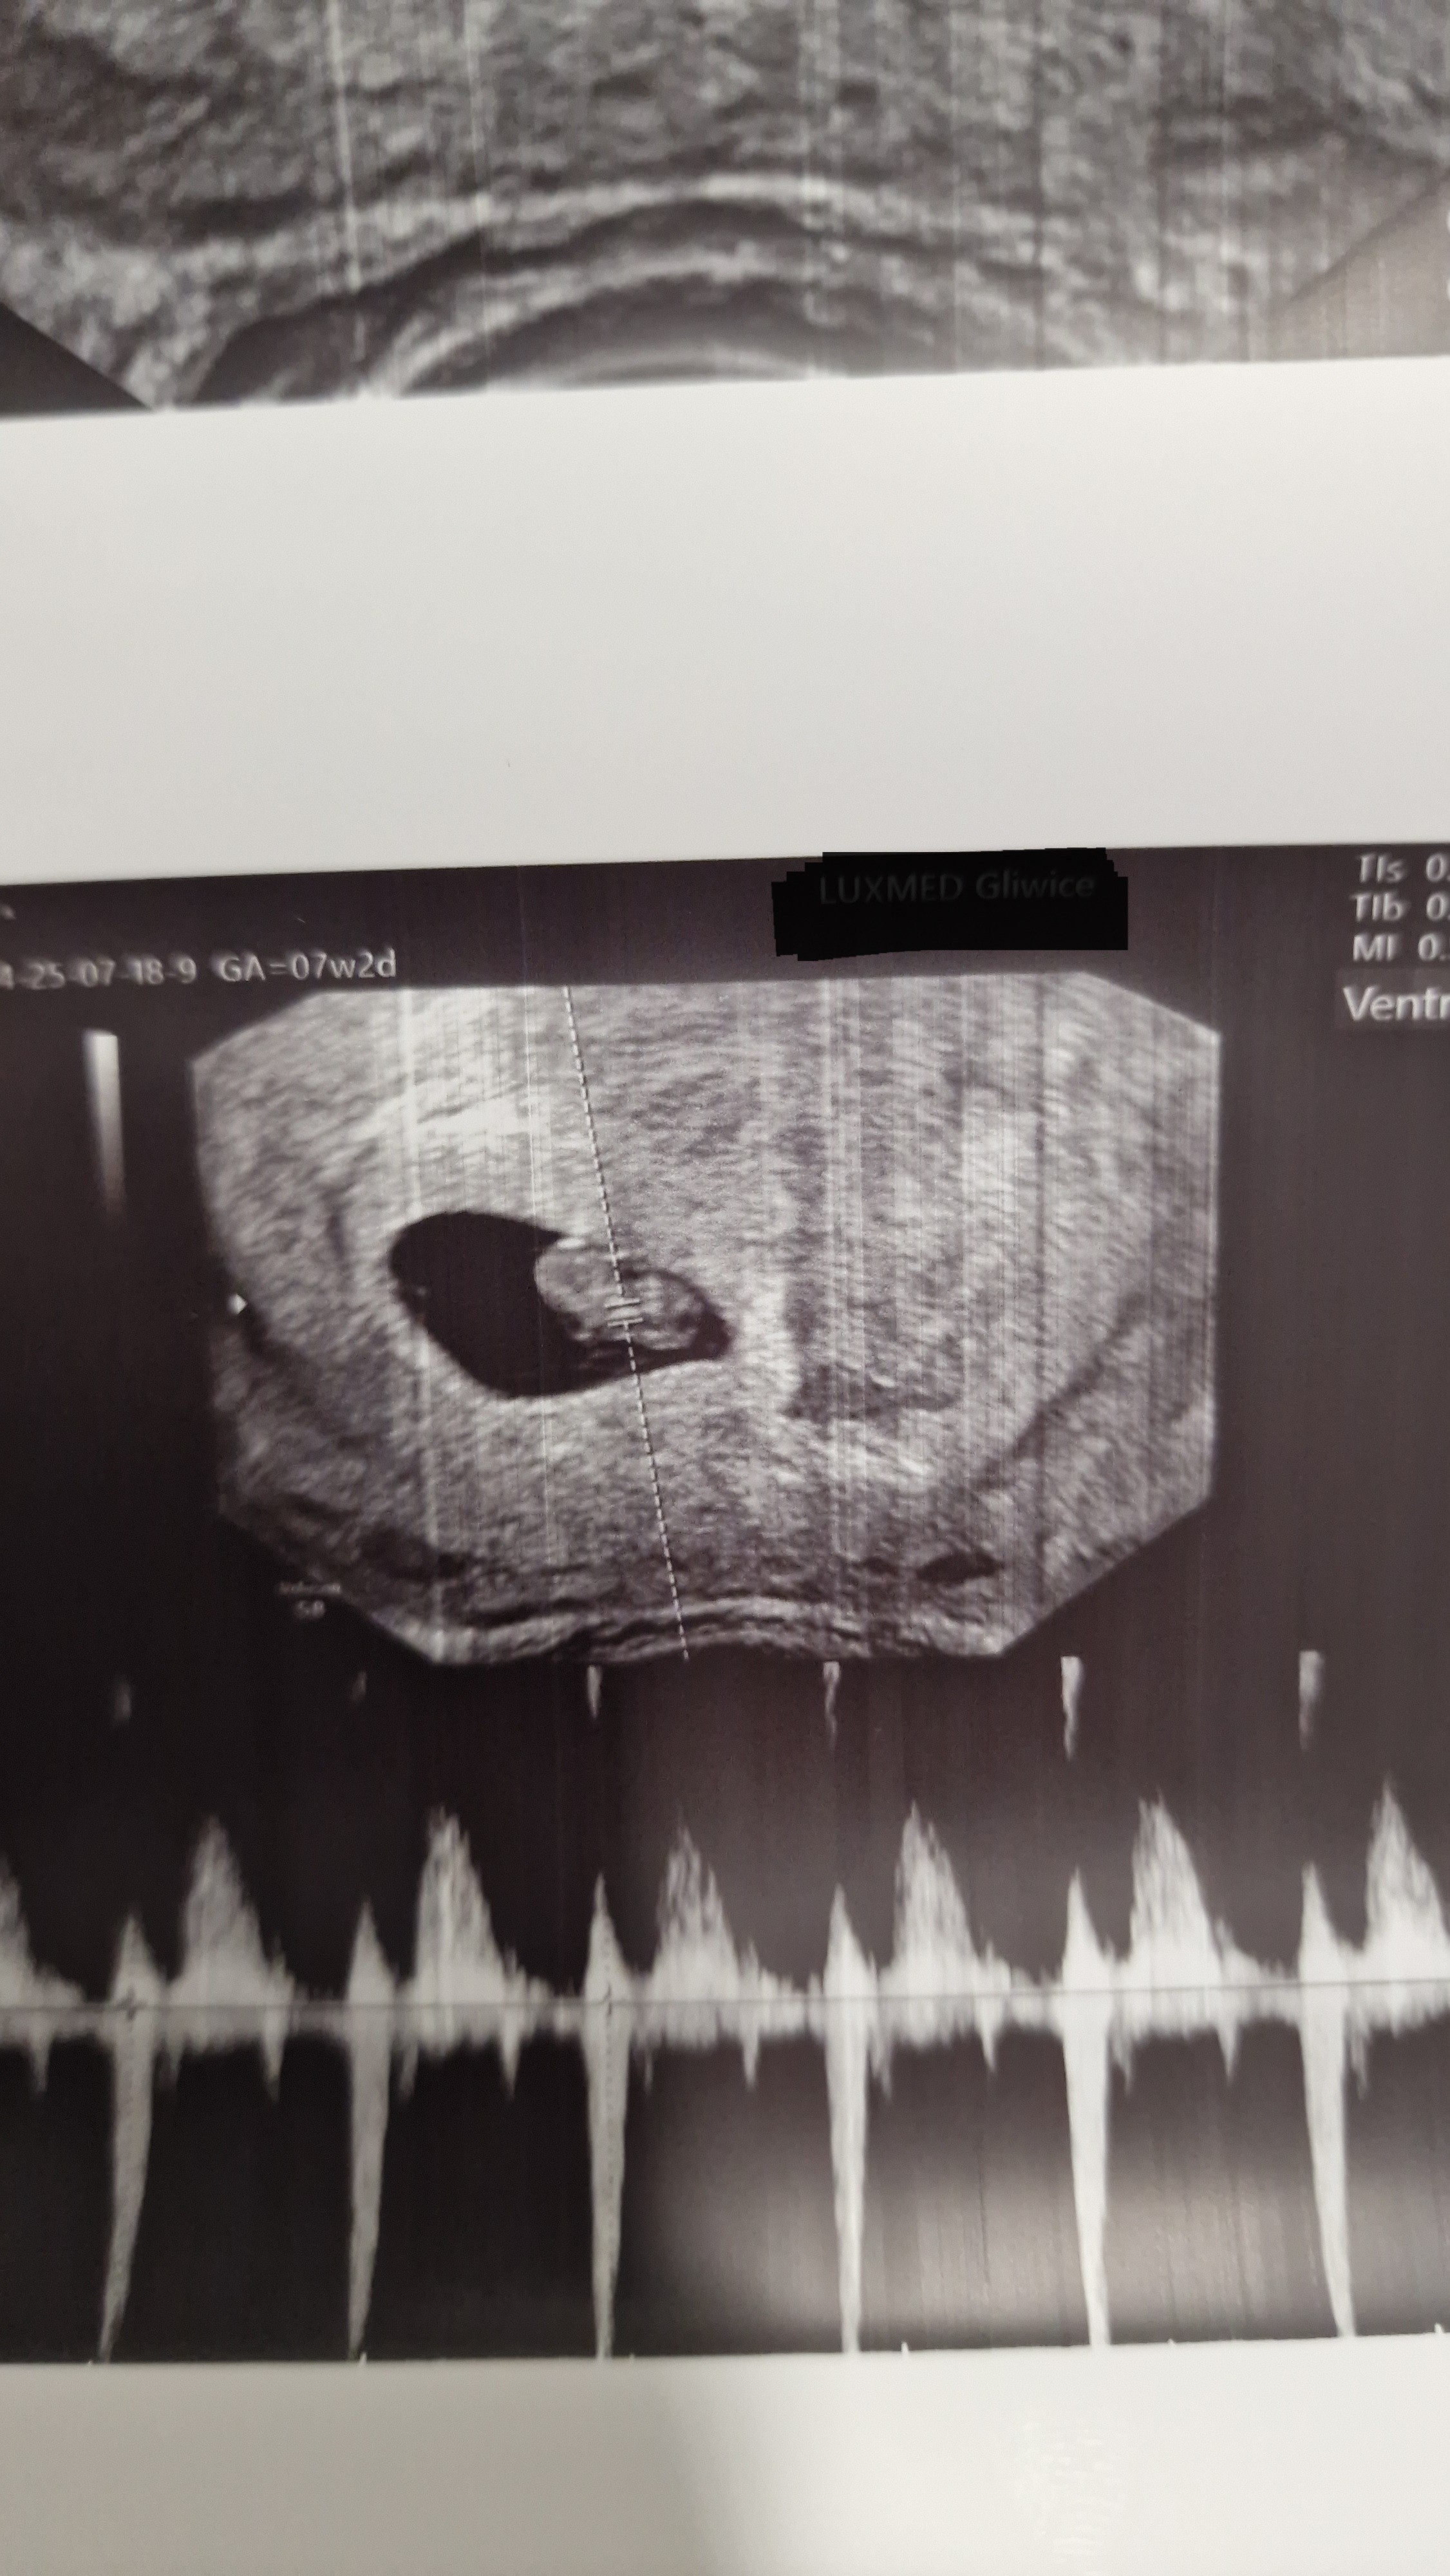

Ja dziś miałam wizytę i jest zarodek z bijącym serduszkiem ❤️

Niestety tuż obok jest krwiak i muszę być ostrożna, nie nosić itd.

1cm człowiek 🥰